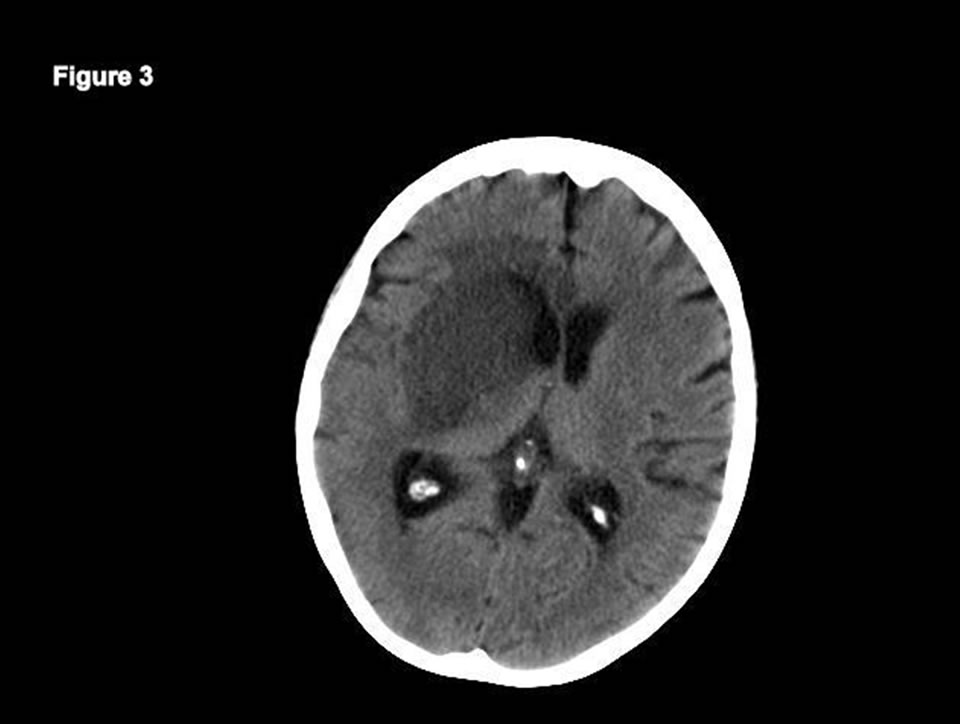

Acute Bilateral Basal Ganglia Lesions and Chorea in a DiabeticUremic

Acute Bilateral Basal Ganglia Lesions and Chorea in a DiabeticUremic Basal Ganglia Hypodensity Bilateral basal ganglia abnormalities are. The basal ganglia and thalamus are paired deep gray matter structures that may be involved by a wide variety of disease. a diffuse hypodensity of bilateral basal ganglia and thalami extending into the brainstem and adjacent cerebral. the term “basal ganglia” refers to caudate and lentiform nuclei, the latter composed of putamen and. Basal Ganglia Hypodensity.

From archneur.jamanetwork.com